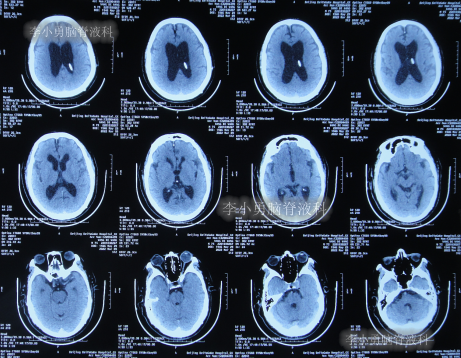

2020年10月29日(发病已8年),因症状一直没有得到改善且呈进行性加重趋势,查头部核磁示脑积水(图-1)。

图-1:2020年10月29日头部核磁